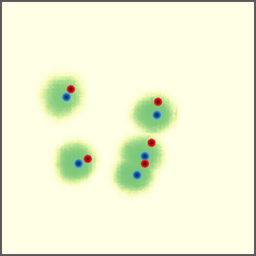

Shift-Invariant Tracking. The POINT network benefits from the shift invariant property of the convolution operation, which makes it less sensitive to the in-plane offset of the DRRs. Figure 8 shows some tracking results from the POINT network. Here the odd rows show the (a) X-ray and (b-d) DRR images. The heatmap below each DRR shows the tracking result between this DRR and the leftmost X-ray image. The red and the blue marks on the X-ray and DRR images denote the POIs. The red and the blue marks on the heatmaps are the ground truth POIs and the tracked POIs, respectively. The green blobs are the heatmap responses and they are used to generate the tracked POIs (blue) according to Equation (7). The numbers under each DRR denote the mPD scores before and after the tracking. As we can observe that the tracking results are consistently good, no matter how much initial offset there is between the DRR and the X-ray image. This shows that our POINT network indeed benefits from the POI convolution layer and provide more consistent outputs regardless of the in-plane offsets.

Refer to caption

(a)

(b) 13.6 \rightarrow 7.3

(c) 22.9 \rightarrow 9.0

(d) 37.1 \rightarrow 7.8

(e)

(f) 19.5 \rightarrow 8.7

(g) 26.0 \rightarrow 9.5

(h) 41.1 \rightarrow 11.4

(b)

(c)

(d)

Figure 8: POI tracking results. (a) X-ray image. (b-d) DRR images with different in-plane offsets. The heatmaps of the tracking results are all aligned with the X-ray images and appear similar, showing the shift-invariant property.